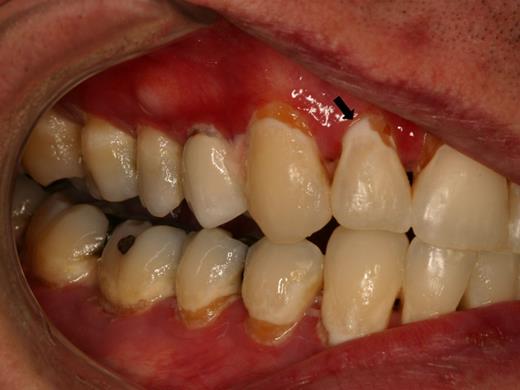

The primary symptom associated with oral mucosal cGVHD is sensitivity to otherwise normally tolerated foods, drinks, and oral hygiene products, with most patients reporting little if any oral discomfort at rest. Foods and drinks that are consistently reported by patients as being painful include those that are spicy (eg, even a very small amount of pepper), acidic (eg, fruits, salad dressing), and hard/rough/crunchy; however, in some patients there is universal sensitivity such that oral intake becomes severely restricted. Although symptoms are generally worse with more severe clinical manifestations, this is not universally true, and patients with only reticular changes may be as or more symptomatic than patients with ulcerations.13 When there are prominent reticular changes affecting the buccal mucosa, patients may report a sensation of mouth tightness and a reduced ability to open the mouth (Figure 5). This should be differentiated from oral tightness because of primary sclerotic cutaneous cGVHD or secondary to mucosal scarring (see “Sclerotic disease”).

cGVHD of the buccal mucosa with extensive and thick hyperkeratosis making the mouth feel “tight” with limited opening.